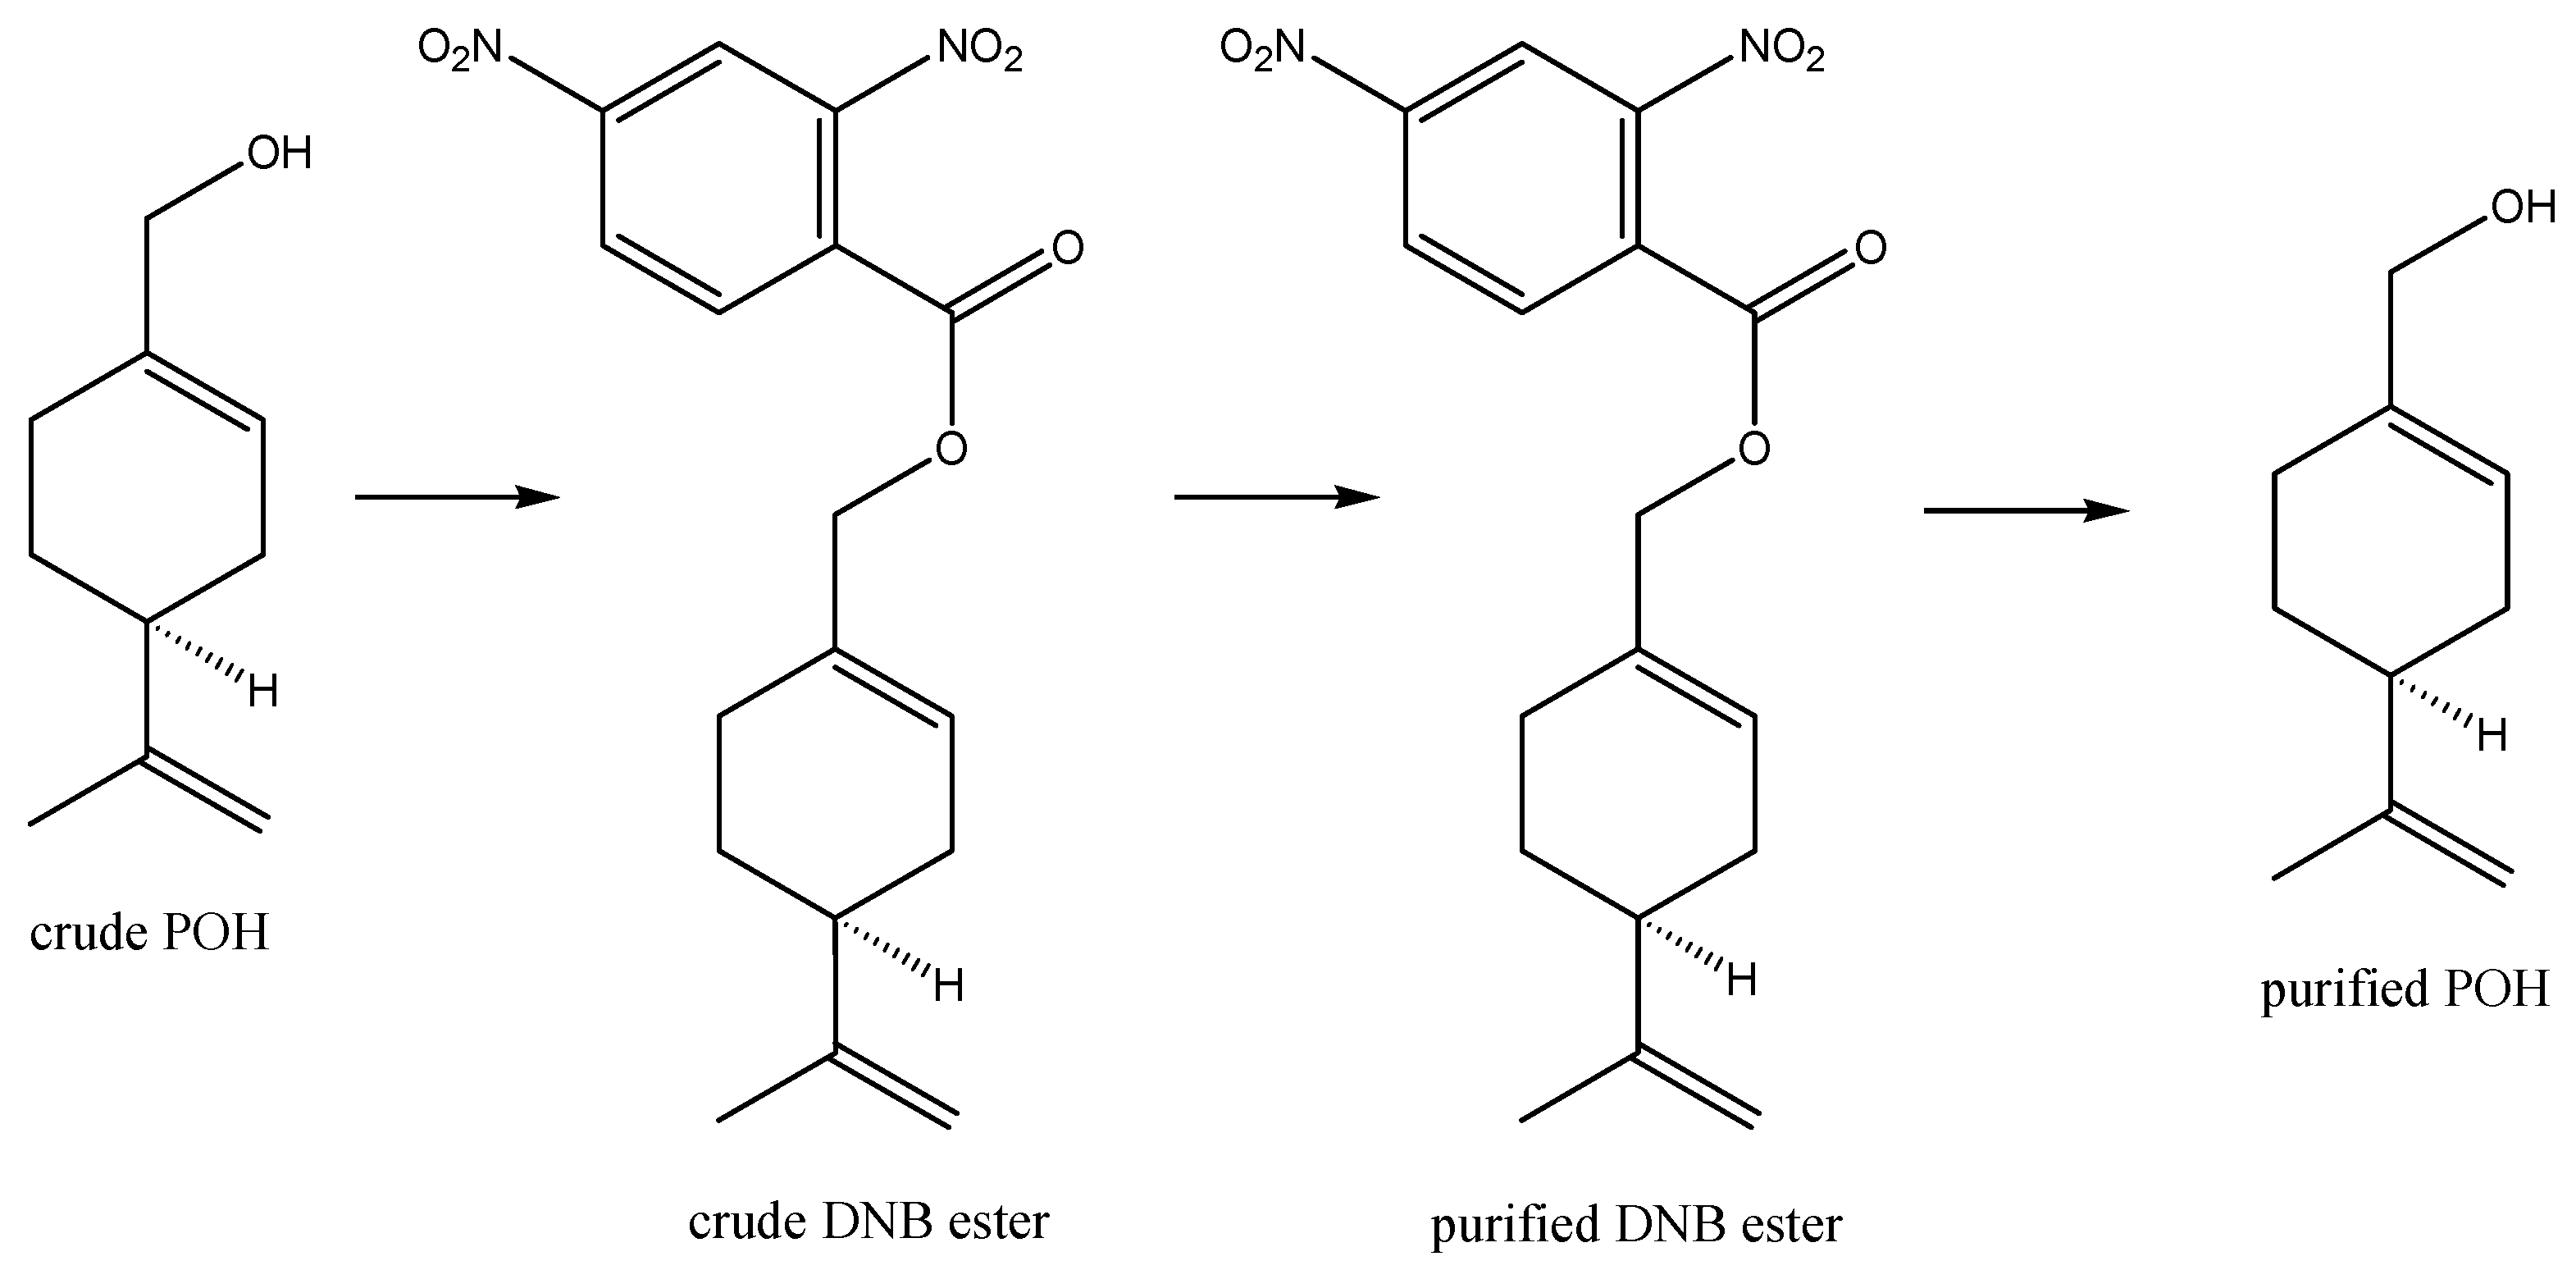

4. Intranasal Perillyl Alcohol

- Erdő, F.; Bors, L.A.; Farkas, D.; Bajza, Á.; Gizurarson, S. Evaluation of intranasal delivery route of drug administration for brain targeting. Brain Res. Bull. 2018, 143, 155–170. [Google Scholar] [CrossRef]

- Keller, L.-A.; Merkel, O.; Popp, A. Intranasal drug delivery: Opportunities and toxicologic challenges during drug development. Drug Deliv. Transl. Res. 2021, 1–23. [Google Scholar] [CrossRef]

- Pardeshi, C.V.; Belgamwar, V.S. Direct nose to brain drug delivery via integrated nerve pathways bypassing the blood-brain barrier: An excellent platform for brain targeting. Epert Opin. Drug Deliv. 2013, 10, 957–972. [Google Scholar] [CrossRef] [PubMed]

- Dhas, N.; Yadav, D.; Singh, A.; Garkal, A.; Kudarha, R.; Bangar, P.; Savjani, J.; Pardeshi, C.V.; Garg, N.; Mehta, T. Direct transport theory: From the nose to the brain. In Direct Nose-to-Brain Drug Delivery; Pardeshi, C.V., Souto, E.B., Eds.; Academic Press: San Diego, CA, USA; Cambridge, MA, USA; Oxford, UK; London, UK, 2021; pp. 15–38. [Google Scholar]

- Khunt, D.; Misra, M. Basic considerations of anatomical and physiological aspects of the nose and the brain. In Direct Nose-to-Brain Drug Delivery; Pardeshi, C.V., Souto, E.B., Eds.; Academic Press: San Diego, CA, USA; Cambridge, MA, USA; Oxford, UK; London, UK, 2021; pp. 3–14. [Google Scholar]

- Laddha, U.D.; Tagalpallewar, A.A. Physicochemical, biopharmaceutical, and practical considerations for efficient nose-to-brain drug delivery. In Direct Nose-to-Brain Drug Delivery; Pardeshi, C.V., Souto, E.B., Eds.; Academic Press: San Diego, CA, USA; Cambridge, MA, USA; Oxford, UK; London, UK, 2021; pp. 39–56. [Google Scholar]

- Gänger, S.; Schindowski, K. Tailoring Formulations for Intranasal Nose-to-Brain Delivery: A Review on Architecture, Physico-Chemical Characteristics and Mucociliary Clearance of the Nasal Olfactory Mucosa. Pharmaceutics 2018, 10, 116. [Google Scholar] [CrossRef] [PubMed] [Green Version]

- Crowe, T.; Greenlee, M.H.W.; Kanthasamy, A.; Hsu, W.H. Mechanism of intranasal drug delivery directly to the brain. Life Sci. 2018, 195, 44–52. [Google Scholar] [CrossRef] [PubMed]

- Djupesland, P.G.; Messina, J.C.; A Mahmoud, R. The nasal approach to delivering treatment for brain diseases: An anatomic, physiologic, and delivery technology overview. Ther. Deliv. 2014, 5, 709–733. [Google Scholar] [CrossRef] [PubMed] [Green Version]